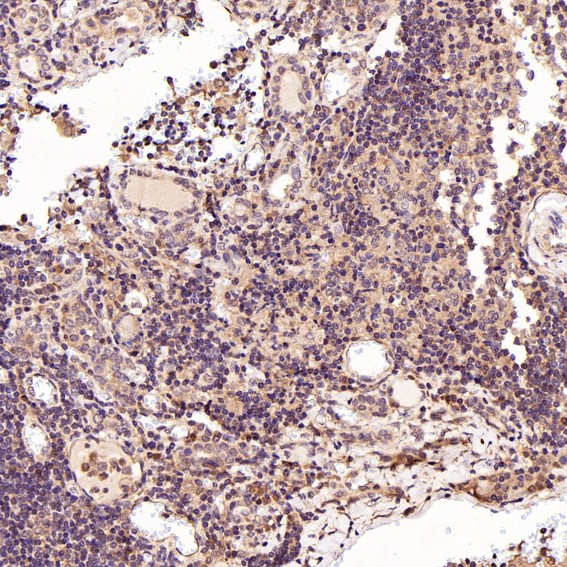

Facts about Mitogen-activated protein kinase 14.

Accordingly, p38 MAPKs phosphorylate a wide assortment of proteins and it has been estimated that they might have approximately 200 to 300 substrates each. A few of the targets are downstream kinases that are activated through phosphorylation and additional phosphorylate additional targets.

Brain, heart, placenta, pancreas and skeletal muscle. Expressed to a lesser extent in lung, liver and kidney.

Cytoplasm. Nucleus.